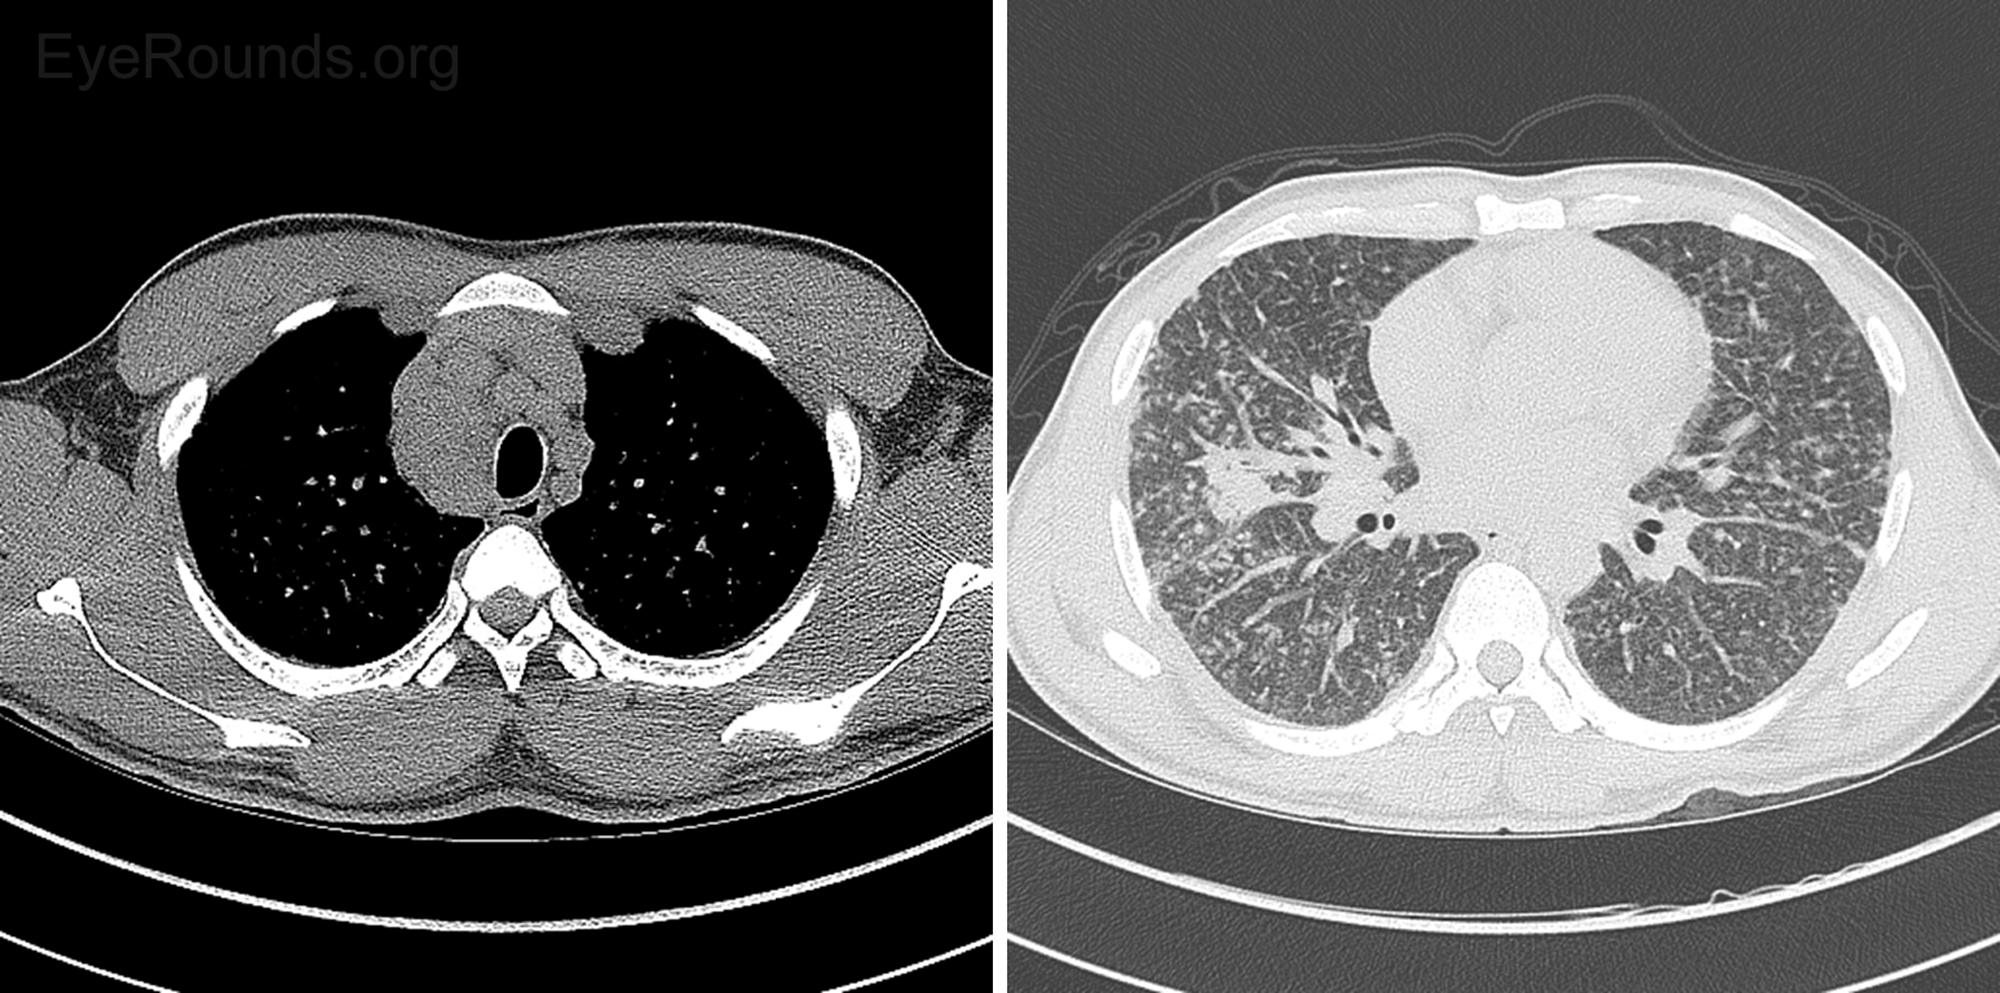

• Computed tomography (CT) of the chest without contrast (Figure 6)

Figure 6: CT Chest without contrast. Diffuse lymphadenopathy was present and nonspecific, but given the diffuse nature was most consistent with systemic disease such as sarcoid or lymphoma. Diffuse prominence of bronchovascular interstitium with associated nodularity was nonspecific. More focal consolidation in the right middle lobe, tree-in-bud nodularity in the inferior right upper lobe, and centrilobular ground-glass nodules suggested more acute inflammatory bronchial process, such as bronchitis. Although a CT pattern of alveolar sarcoid can present with ground-glass opacities, the pattern the patient presented with was more typical of centrilobular bronchitis.